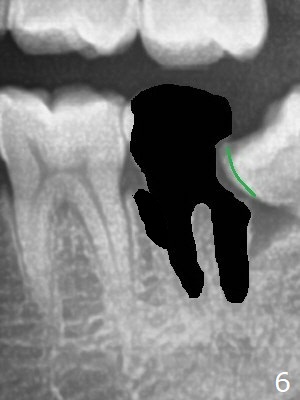

A 36-year-old man with poor dentition (smoker 1/4 ppd) requests extraction of sympto-matic teeth (#18 and 32, Fig.1). A half of Osteogen Plug is placed at #32 post extraction. To extract #18, the tooth has to be sectioned (Fig.2 red). The mesial portion is removed easy, while the distal one requires removing the mesial surface of #17 (Fig.2 green). Vanilla bone is placed after extraction (Fig.3), covered by 8x8 mm Amnion-Chorion Allograft and sutured with 4-0 PGA. Four months later, the mesial surface of #17 will be trimmed (Fig.4 black area) so that surgical guide metal sleeve (green) will be seated in the neutral position of the edentulous area. After extraction (Fig.5 black), the distal portion of the mesial crest will be resorbed, leading to gingival papilla atrophy and food impaction (Fig.6). Keeping the mesial portion of the root (Fig.7 *, socket shield) is able to prevent mesial crestal bone loss. The immediate implant will be placed ~ 2 mm short of the depth and checked whether it touches the retained root or not.